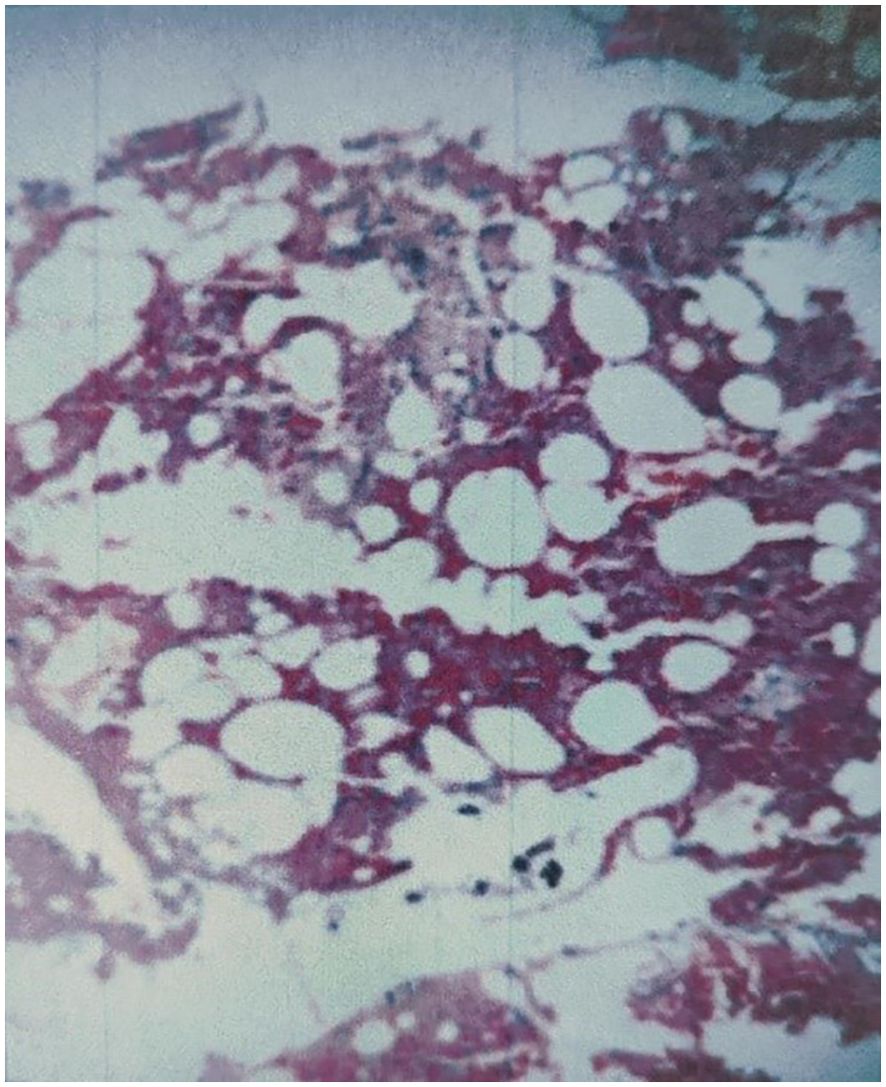

Pathological examination of tissue samples supported the diagnosis of AVH (Figure 5). The patient’s bilateral iliopsoas muscle strength recovered to grade V, and the pain and numbness symptoms were greatly alleviated, with a postoperative VAS of 2. Follow-up at 1.5, 6, and 12 months revealed good recovery of muscle strength and sensation, with no signs of recurrence (Figure 6).

Figure 5

Microscopic view of tissue showing clusters of irregularly shaped white cells against a background of red stained areas, possibly indicating fatty tissue or adipocytes.

Figure 5. The pathological examination was consistent with AVH. Photomicrograph (H&E stain) revealed multiple thin-walled, dilated, blood-filled vascular channels scattered between bony trabeculae.